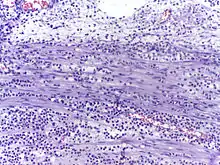

In autopsy, the presence of neutrophils in the heart or brain is one of the first signs of infarction, and is useful in the timing and diagnosis of myocardial infarction and stroke.

- Neutrophils are seen in a myocardial infarction at approximately 12–24 hours,[59] as seen in this micrograph.